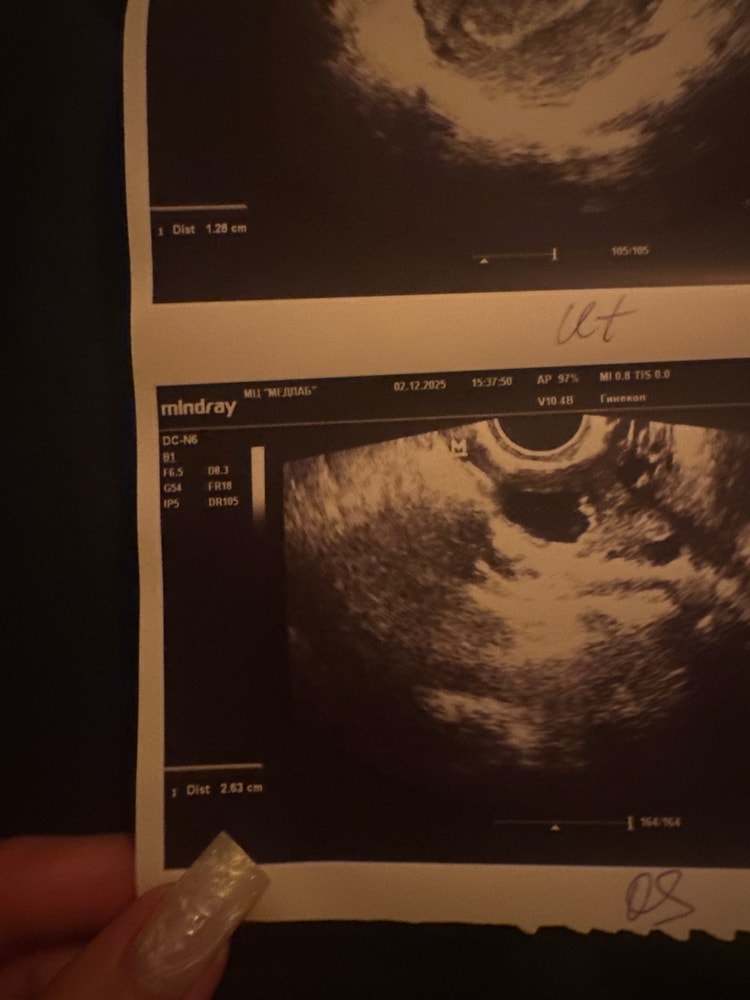

Ольга Морозова, ИзображениеУ меня размер написан сбоку 2,63

Кити, Изображениепосмотрите , пожалуйста, уже, боюсь, что цикл ануволотерный

Виктория, Изображение